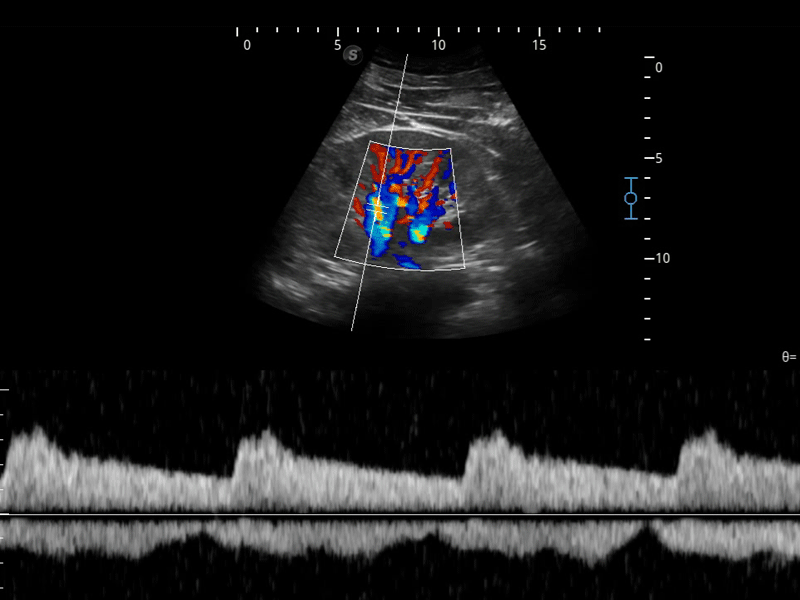

造影成像

造影成像功能和定量分析工具包使医生能够更好的评估血流灌注情况。独特的动态声压控技术有效控制造影剂的声压,保证更长的造影剂持续时间,更好的观察病变灌注的延迟相位。